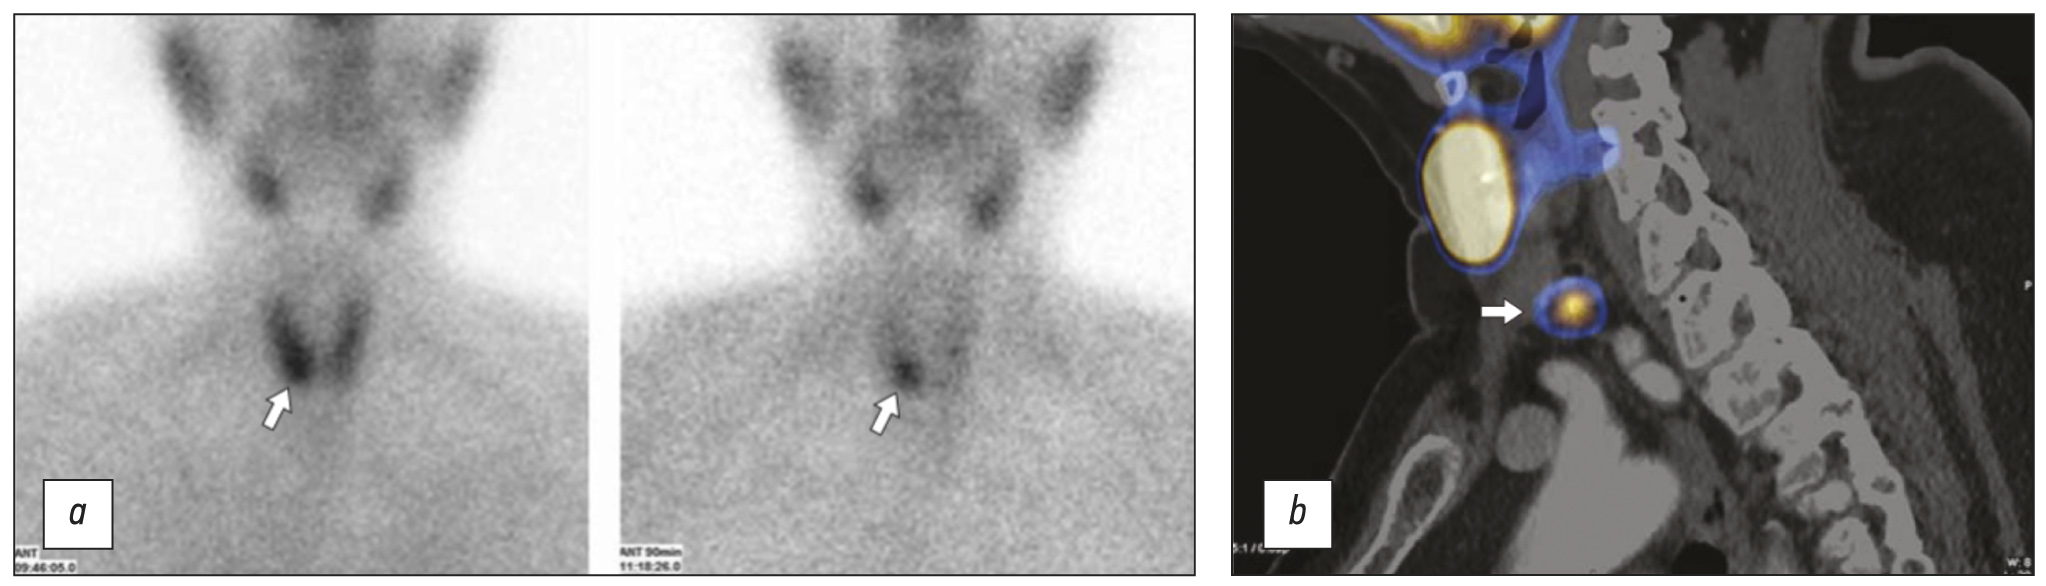

HPT 局部诊断信息量最大的方法是使用 99mTc-MIBI 进行放射性核素诊断,尤其是在 SPECT/CT 模式下(图 4)。 平均而言,该方法的灵敏度达到 88%(阳性预测值为 96%)[20]。

图 4。使用 99mTc-MIBI(technetril)进行放射性核素研究:a - 两相平面闪烁扫描(早期和延迟扫描):甲状旁腺的形成在右叶(箭头)的投影中可视化,放射性药物的持续积累增加关于延迟扫描; b - 单光子发射计算机断层扫描,结合计算机断层扫描,99mTc-MIBI:在左叶下极(箭头)后面和向下形成甲状旁腺,积累放射性药物。